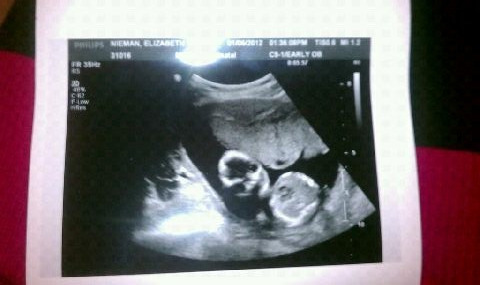

Incompetent: lacking qualification or ability. Yeah, that sounds accurate. Along with my misbehaving uterus I also have an incompetent cervix – go figure.